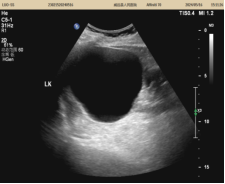

70岁的罗先生觉得左腰部不舒服有一段时间了,在几年前的体检中发现左肾有一个8.2x197.5px的囊肿,由于囊肿过大,医生建议手术治疗。因年龄偏大,担心手术风险,所以对手术治疗一直心存顾虑。他听说威远县人民医院超声科有不手术就可以治疗囊肿的方法,抱着了解的心态就来了。超声科副主任医师何玉周向罗先生详细解释了超声引导下经皮囊肿穿刺抽液硬化治疗术,并对其进行了囊肿硬化治疗。术前术后即刻对比,效果立竿见影,囊肿消失不见,罗先生避免了开放手术和腹腔镜手术,感到十分的满意。